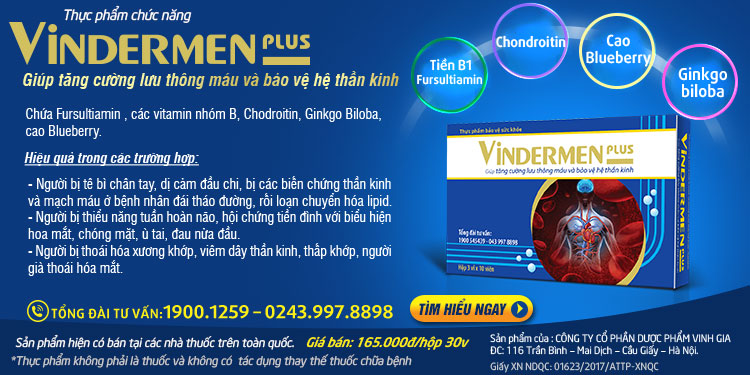

- Tăng cường lưu thông máu và hồi phục rễ thần kinh, ngăn chặn tổn thương mạch máu, thần kinh do thoái hóa đốt sống cổ bằng sản phẩm chứa Fursultiamin, Chondroitin, Ginkgo Biloba và cao Blueberry.

Trên đây chính là giải pháp toàn diện giúp điều trị hiệu quả bệnh thoái hóa đốt sống cổ.